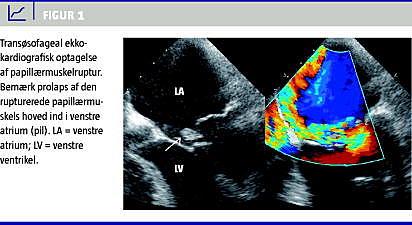

Tidlig diagnose, der bedst stilles med transøsofageal ekkokardiografi (Figur 1 ), prompte stabilisation med vasodilatorer og aortaballonpumpe, er obligat for forberedelse til kirurgisk intervention med revaskularisering og klapsubstitution [5, 9, 19, 21, 22].

Med transtorakal ekkokardiografi (TEE) kan man påvise hjerterupturer med høj sensitivitet, men kun moderat specificitet med en del falsk positive fund [11, 12]. Ved ruptur af venstre ventrikel er perikardial effusion og en overliggende perikardial trombe hyppige fund [11, 12], mens der ved aneurismer ses karakteristisk akinesi og/eller dyskinesi af venstre ventrikel og bedst med brug af kontrast [13]. Det er vigtigt at skelne mellem medfødte kongenitte defekter og postinfarkte ventrikelseptumdefekter [14]. Diagnosen papillærmuskelruptur skal oftest stilles med transøsofageal ekkokardiografi (TEE) [17].